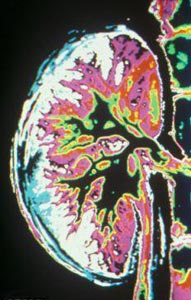

عضو هیات علمی دانشگاه علوم پزشکی جندی شاپور اهواز گفت: ادرار از کلیه وارد میزنای شده و سپس به مثانه منتقل می‌شود و در صورتی که ضایعه‌ای در کلیه موجب خون‌ریزی شود، خون با ادرار مخلوط شده و از بدن خارج می‌شود.

دکتر محمدعلی حسینی در گفت‌وگو با ایسنا، اظهار کرد: سنگ‌های کلیه و مثانه، انواع عفونت‌ها، تومور یا سرطان و ضربه خوردن به کلیه موجب مشاهده شدن خون در ادرار می‌شوند.

وی افزود: عفونت‌های مزمن که در کلیه و مثانه ایجاد می‌شود، موجب سوزش، خارش و تکرر ادرار می‌شود و مدت بیماری نیز طول می‌کشد ولی عفونت‌های حاد سریع ایجاد شده، پیشرفت کرده و سریع هم از بین می‌روند. در هر یک از این دو حالت ممکن است خون در ادرار دیده شود.

وی تصریح کرد: عفونت‌ها و سنگ‌های کلیوی و سنگ مثانه می‌توانند زمینه‌ای برای بروز سرطان باشند بنابراین تشخیص به موقع این بیماری‌ها اهمیت دارد.

حسینی ادامه داد: این موارد، در صورت ادامه بیماری ممکن است موجب تخریب دستگاه اداری شوند. دیده شدن خون در ادرار می‌تواند نشانه‌ای از هر کدام از این بیماری‌ها باشد.